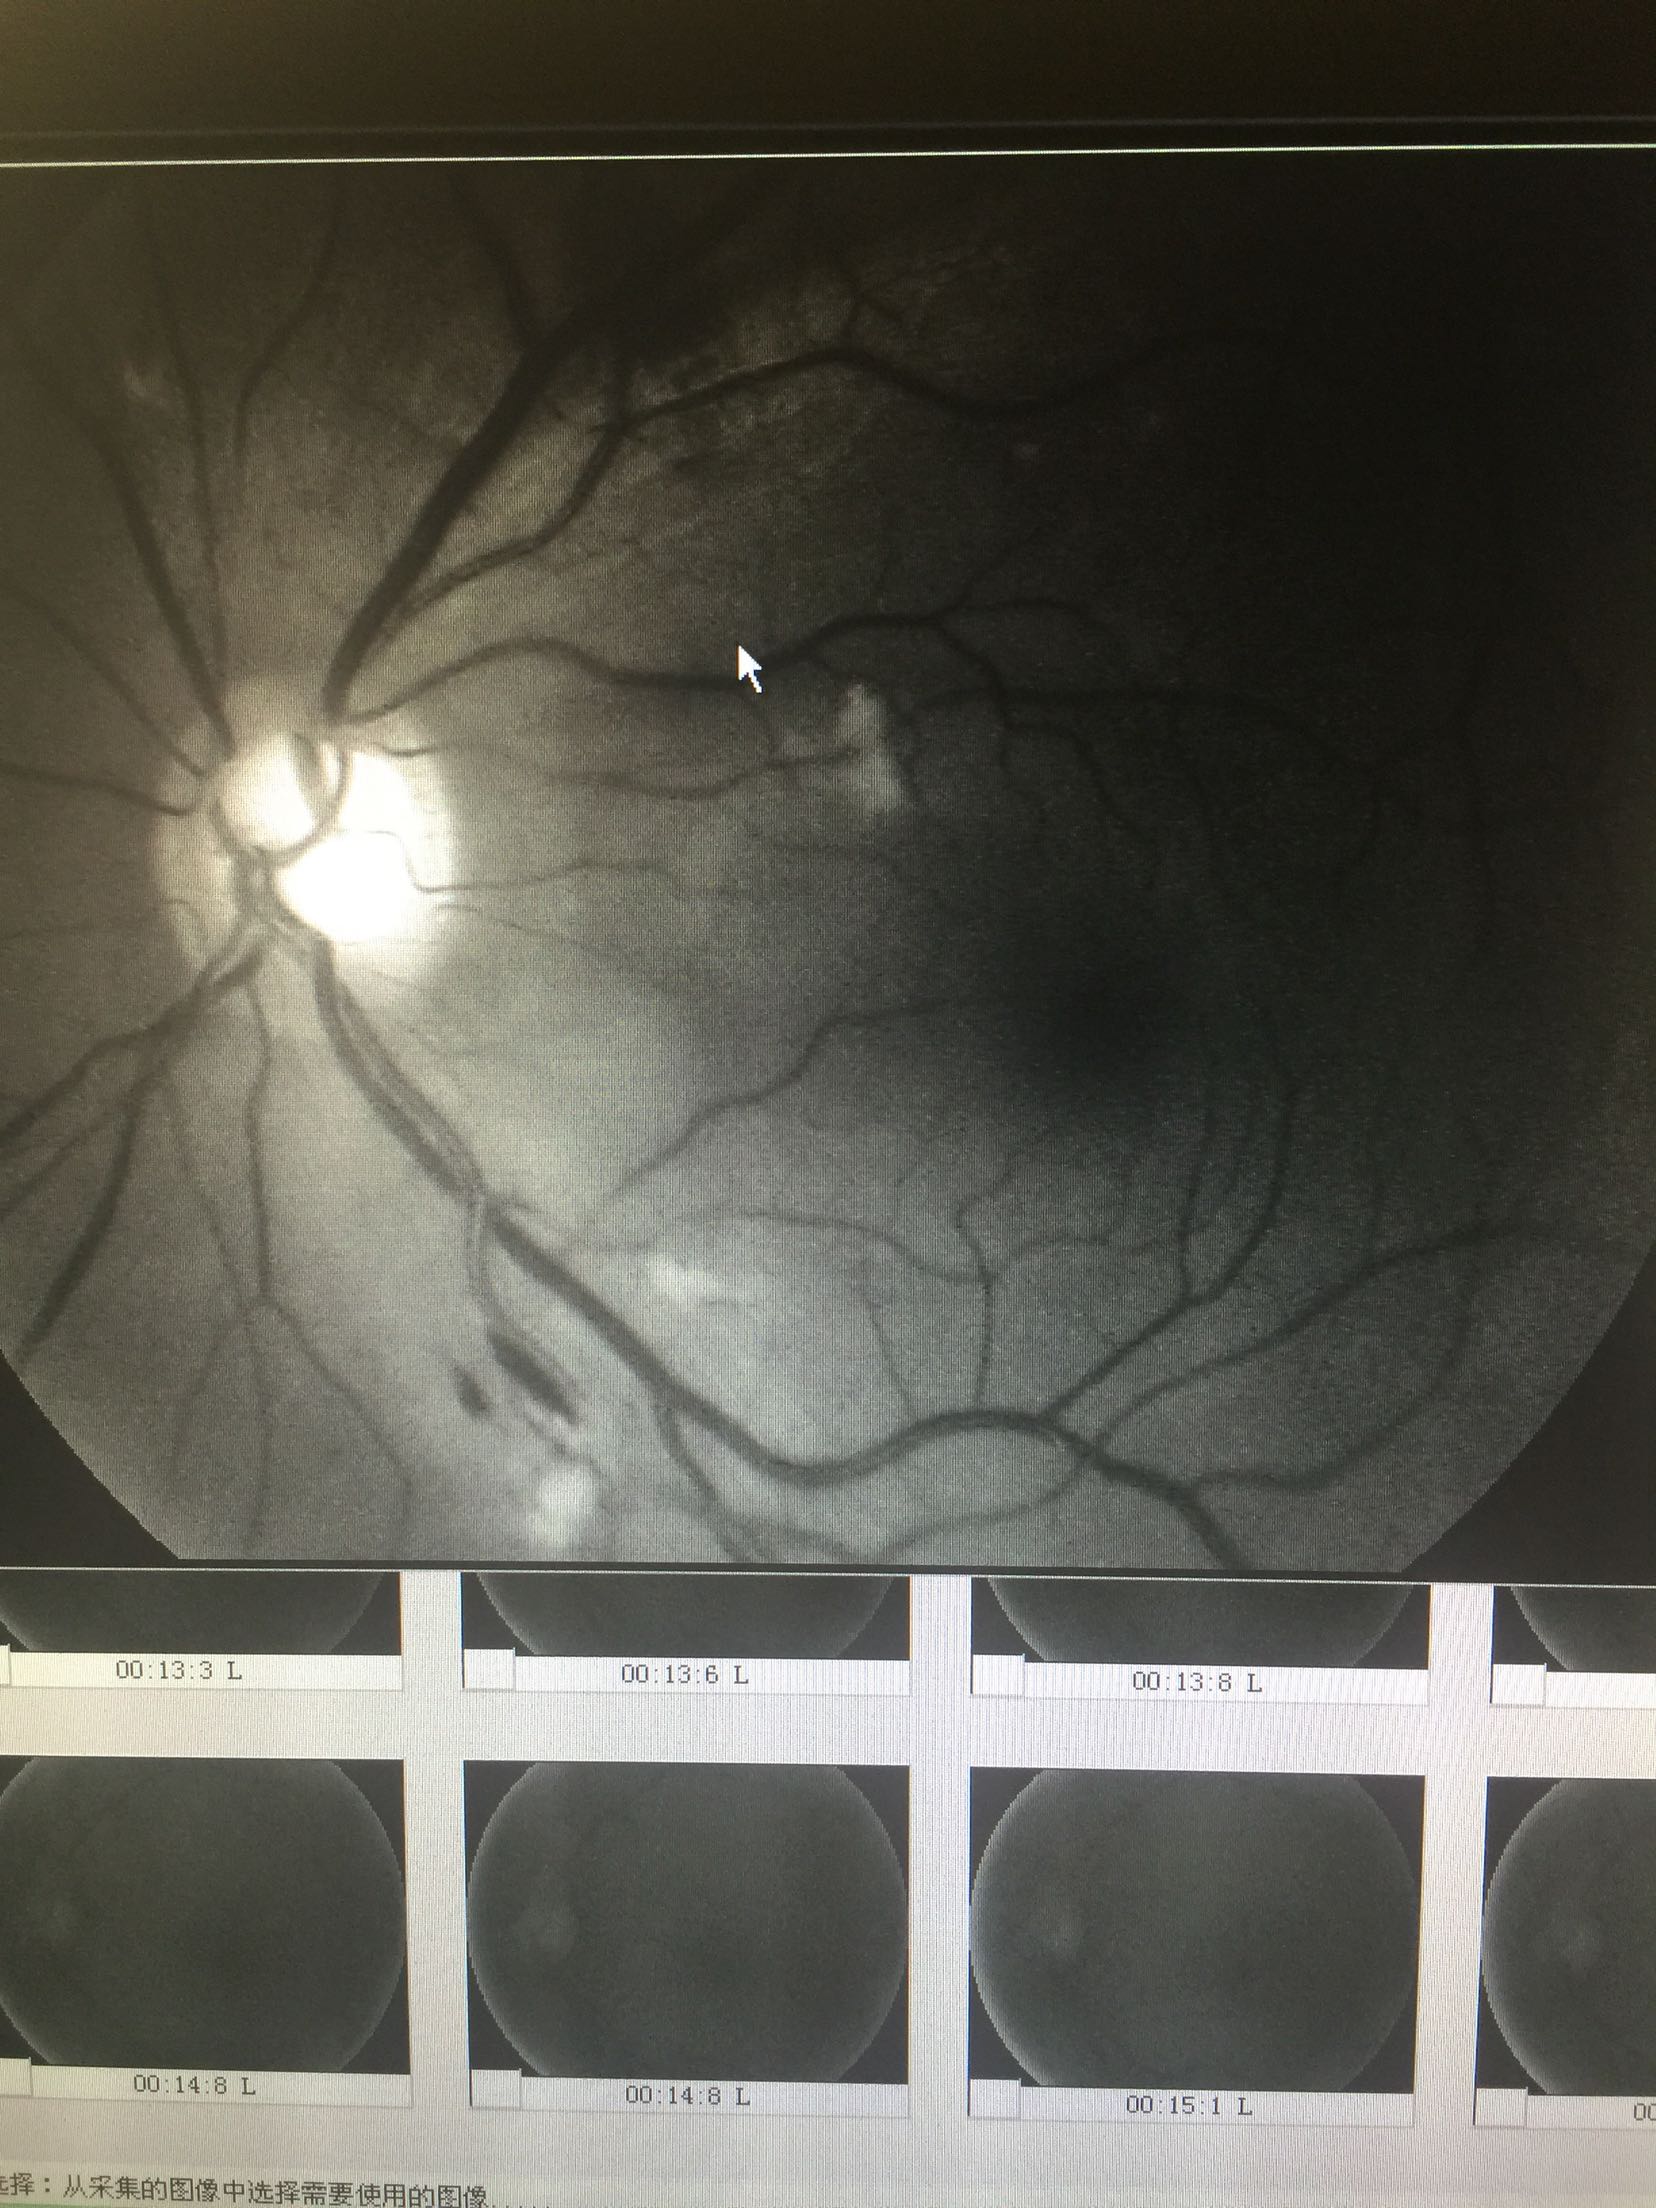

视力: 右眼0.6 左眼0.5 双眼睑无水肿,结膜无充血,角膜透明,前房正常,瞳孔圆,对光反射可,虹膜纹理清,晶体轻度浑浊,眼底视盘界清色可,黄斑区中心凹反光还可,网膜散在片状出血及硬性渗出 眼压:13/17 血压100/70mmhg 随机血糖:6.2

心电图:窦性心律,67次/分 造影:左眼动脉充盈时间为23秒,静脉充盈时间为27.2秒,双眼全视网膜可见片状荧光遮蔽及黄白色硬性渗出,早期双眼全视网膜散在点状高荧光,晚期有荧光渗漏

双眼糖尿病视网膜病变 药物促进血液吸收,改善眼底循环,视网膜光凝治疗